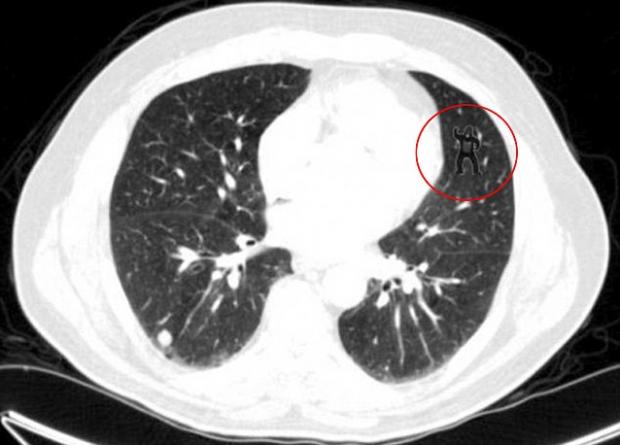

Un studiu psihologic condus de cercetătorii unui spital din SUA a arătat că peste 83% dintre radiologi nu au văzut gorila care apare în imaginea de mai jos. Şi asta cu toate că au privit-o în mod insistent şi repetat.

Studiul are ca scop scoaterea în evidenţă a „orbirii neintenţionate”, mai exact a faptului că radiologilor le pot scăpa detalii care se află chiar în faţa ochilor.

Testul gorilei a fost realizat cu ajutorul a 24 de radiologi care au fost rugaţi să examineze radiografiile a cinci pacienţi (4 sănătoşi şi unul care suferea de cancer la plămâni), arată Daily Mail.

Primele patru radiografii aparţineau persoanelor sănătoase. Gorila era „ascunsă” în 5 imagini consecutive dintr-un calup de 239 de imagini cu radiografii ale persoanei bolnave.